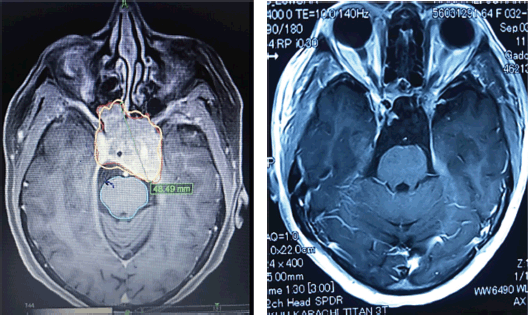

During the follow-up period, only 257 participants provided MRI scans, representing 92.4% of the cohort. Among these individuals, 202 (78.6%) had a reduction in tumour volume, 13 (5.1%) had complete resolution of enhancing lesion and 42 (16.3%) had no interval change in tumour size throughout the follow-up period (Figure 3a and b). We observed that post-CK SRS tumour reduction was more in the larger GTV group (p-value = 0.068). Furthermore, there was no statistically significant correlation between post-CK SRS radiological outcomes and tumour type or radiosurgery parameters (Table 3).

Figure 3. (a): A case of large pituitary macroadenoma before receiving CyberKnife radiosurgery. (b): Near complete resolution of pituitary macroadenoma of the same patient after receiving CyberKnife radiosurgery in the follow-up period.